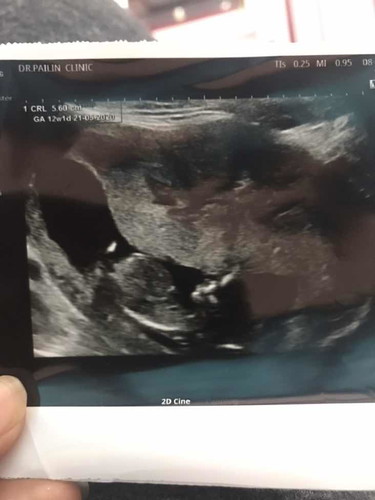

คือเราเพิ่งไปซาวด์น้องมา แล้วสังเกตุเห็นพุงน้องดูโตแบบในภาพ ถือว่าปกติไหมคะ ถามคุณหมอแล้ว หมอบอกว่าปกติค่ะ พอดีเรากับสามีเป็นพาหะธาลัสซีเมียทั้งคู่ เลยกลัวๆค่ะ แม่ๆบ้านไหนเป็นแบบนี้บ้างคะ